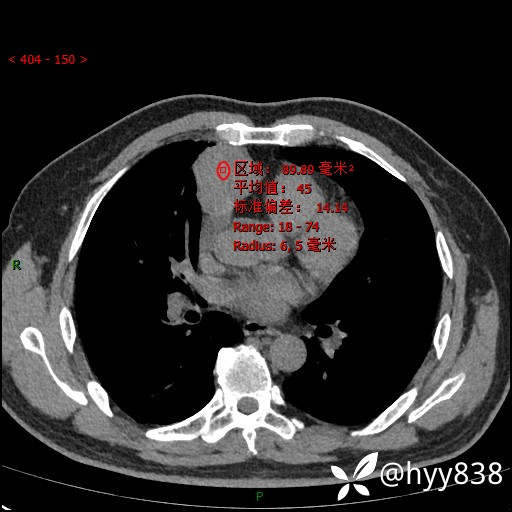

各期CT值